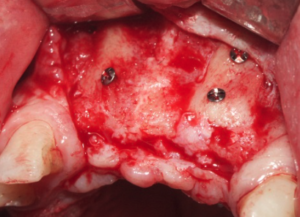

Estructura Subperióstica con carga inmediata maxilar

Paciente con atrofia total del hueso del maxilar que precisa rehabilitación. Se le realizó tratamiento con estructura subperióstica y el mismo día se le colocaron unos dientes fijos provisionales sobre la estructura.